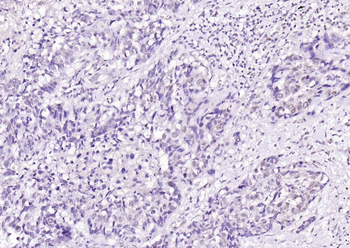

100 μl, 50 μl, 25 μl - Rad51 Recombinant Rabbit Monoclonal Antibody [orb608069]Featured

IF, IHC-Fr, IHC-P, WB

Human, Mouse, Rat

Mouse, Rat

Rabbit

Recombinant

Unconjugated

50 μl, 100 μl - KLF4 Recombinant Rabbit Monoclonal Antibody [orb608075]Featured